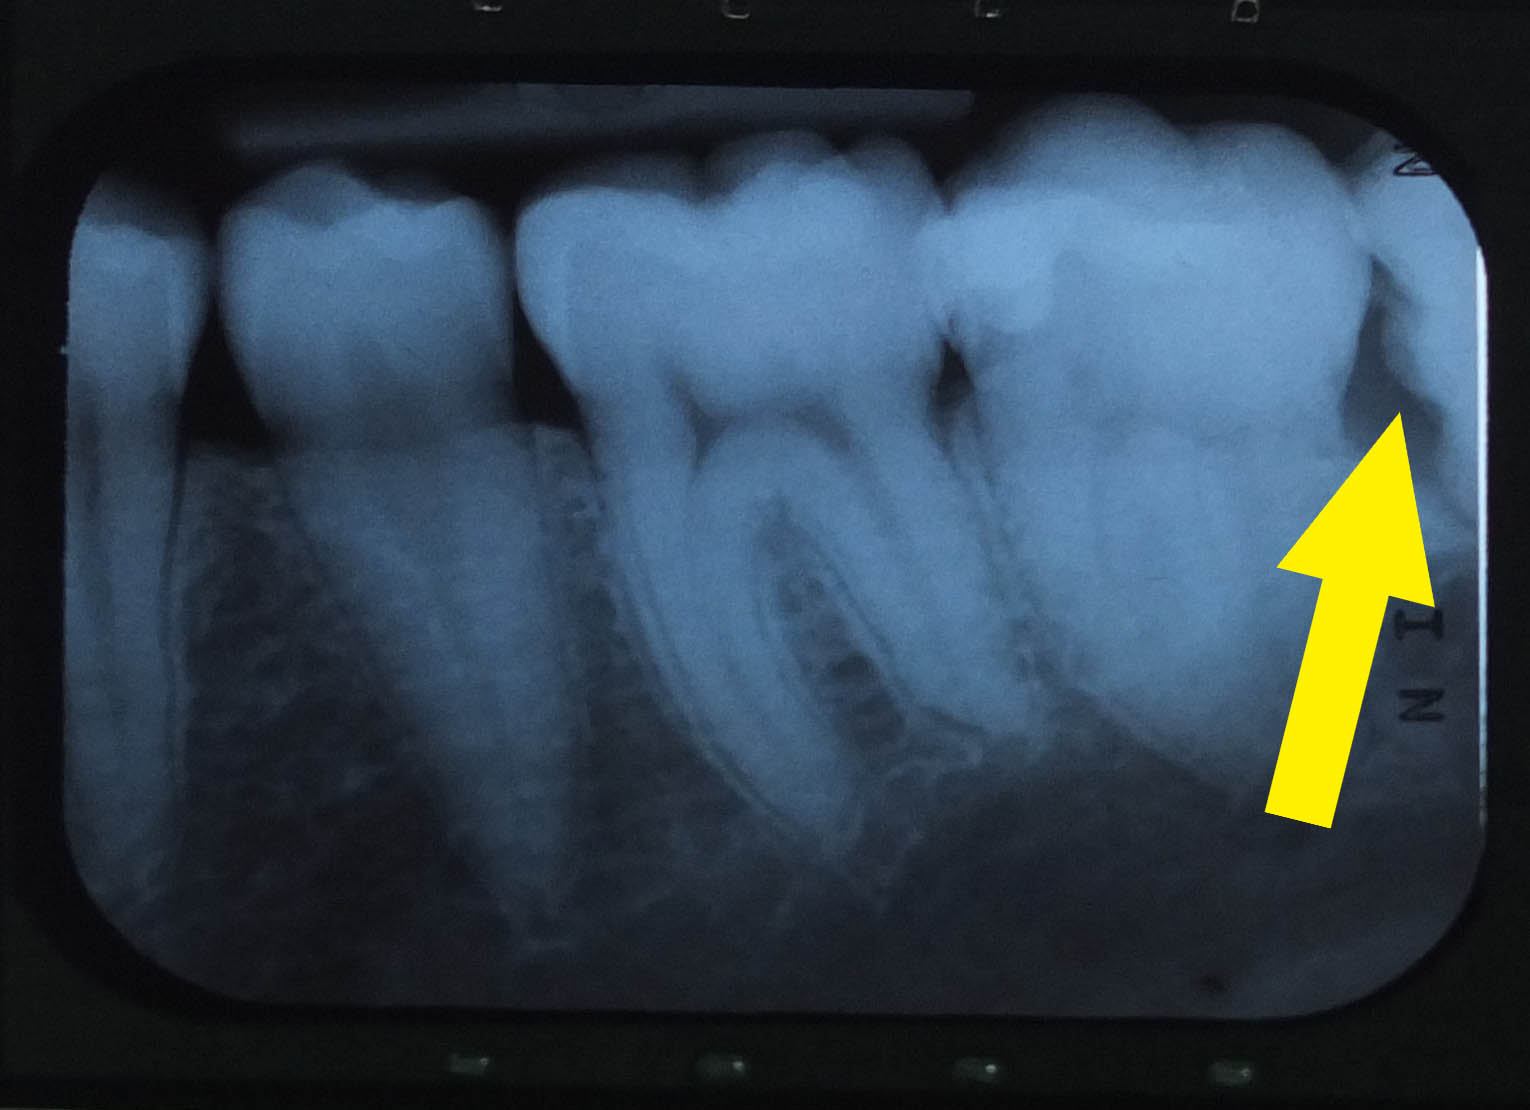

Kävin hammaslääkärisä. Vai oliks se hammashoitajalla? No kumminki tarttee sit mennä myähemmin leikkauttamaan pois alemmat viisaurenhampaat. Kuvasa näkkyy millai se hammas puskee päin muita. Kuukauren ko oon ollu jo puremati vasemmalla pualla leukaa, ni alkaa tähän jo tottua. Eli ei mittään kiirutta poistamisen kans...